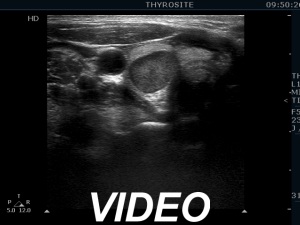

Ultrasonography. The thyroid was echonormal. There was a hypoechoic mass within the lower pole of the right lobe. The lesion was surrounded by thyroid tissue throughout.